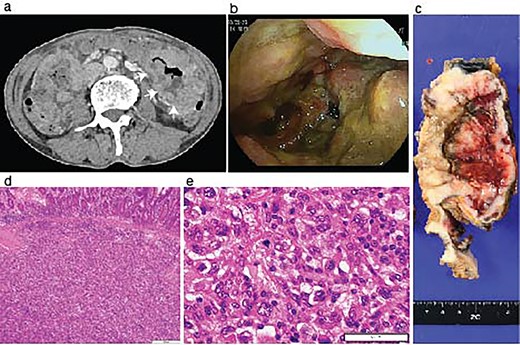

During the follow-up period, the patient presented with progressive anemia and general fatigue. Seven months after the lung surgery, the blood hemoglobin dropped to 6.8 mg/dl from 10.6 mg/dl at 2 months after the lung surgery. The patient was hospitalized, and a red blood cell infusion was performed. As fecal occult blood was consistently observed after the lung operation, another endoscopic examination of the upper and lower digestive tract was scheduled. In the meantime, the patient demonstrated a sudden onset of left side severe abdominal pain. The emergent enhanced CT scanning revealed a large abdominal mass in the left abdominal cavity (Fig. 2a). The subsequently performed small intestinal endoscopy revealed a tumor in the jejunum (Fig. 2b), and the biopsy of the tumor demonstrated the metastasis of the lung cancer. The partial resection of the jejunum including the metastatic lesion followed by end-to-end anastomosis was performed 8 months after the lung operation. The pathological diagnosis of the jejunum tumor was pleomorphic carcinoma, which was identical to the primary lung cancer (Fig. 2c-e). After 1 month of the second surgery, the patient again showed abdominal pain. The gastroscopy examination revealed a gastric tumor in the stomach wall with blood wheezing. Distal gastrectomy was performed 10 months after the lung operation. Some peritoneal nodules suspected of dissemination were also resected. The pathological diagnosis of the gastric tumor and peritoneal nodules was also pleomorphic carcinoma.

Identification of a metastatic intestinal tumor after lung surgery. An abdominal enhanced CT-scanning revealed a large mass lesion suggestive of small bowel involvement (a, arrows). A jejunum tumor was found in intestinal endoscopy (b). A surgical specimen of the metastatic lesion of the jejunum (c). H&E staining of the jejunum tumor showed submucosal malignant cells (d) with pleomorphic features compatible with the primary pleomorphic lung carcinoma (e).